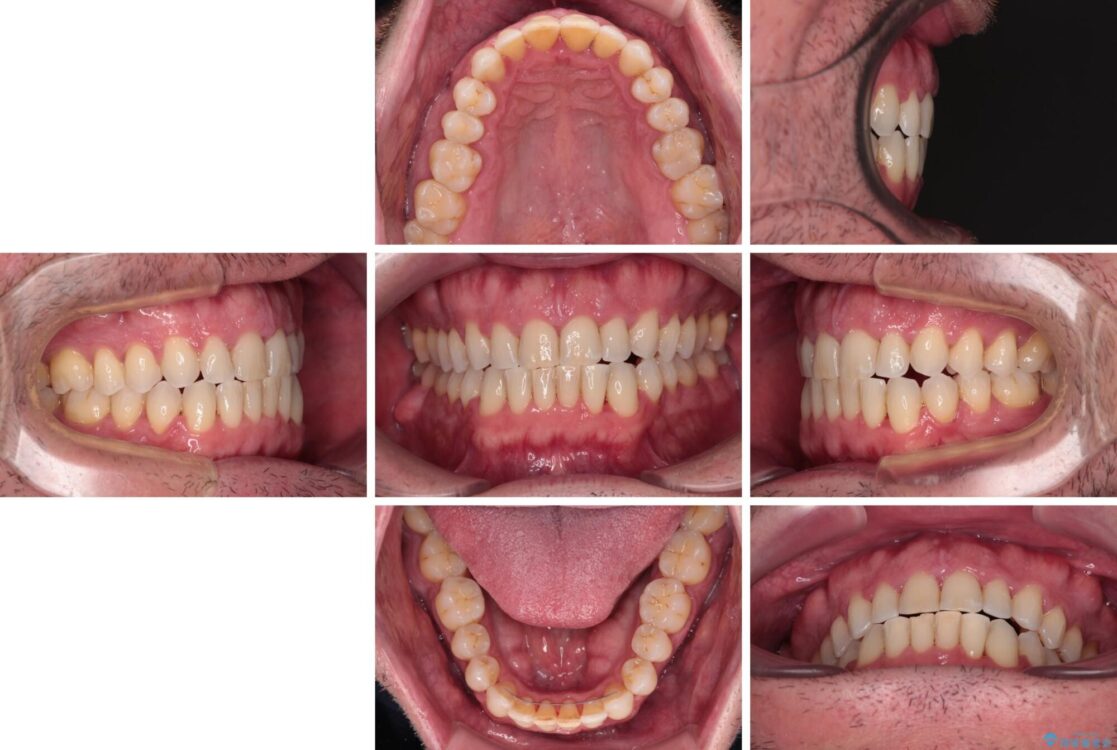

治療後について

舌のトレーニング自体は簡単なものですが、無意識下でも舌が突出しないようにしなければならないため、毎日継続することが最大の難関です。

時間はかかりましたがトレーニングを頑張ってくださり、無事に前歯を接触させることができました。

治療後

• 前歯でものを噛みきりたい 目立たない装置でのワイヤー矯正 治療後画像